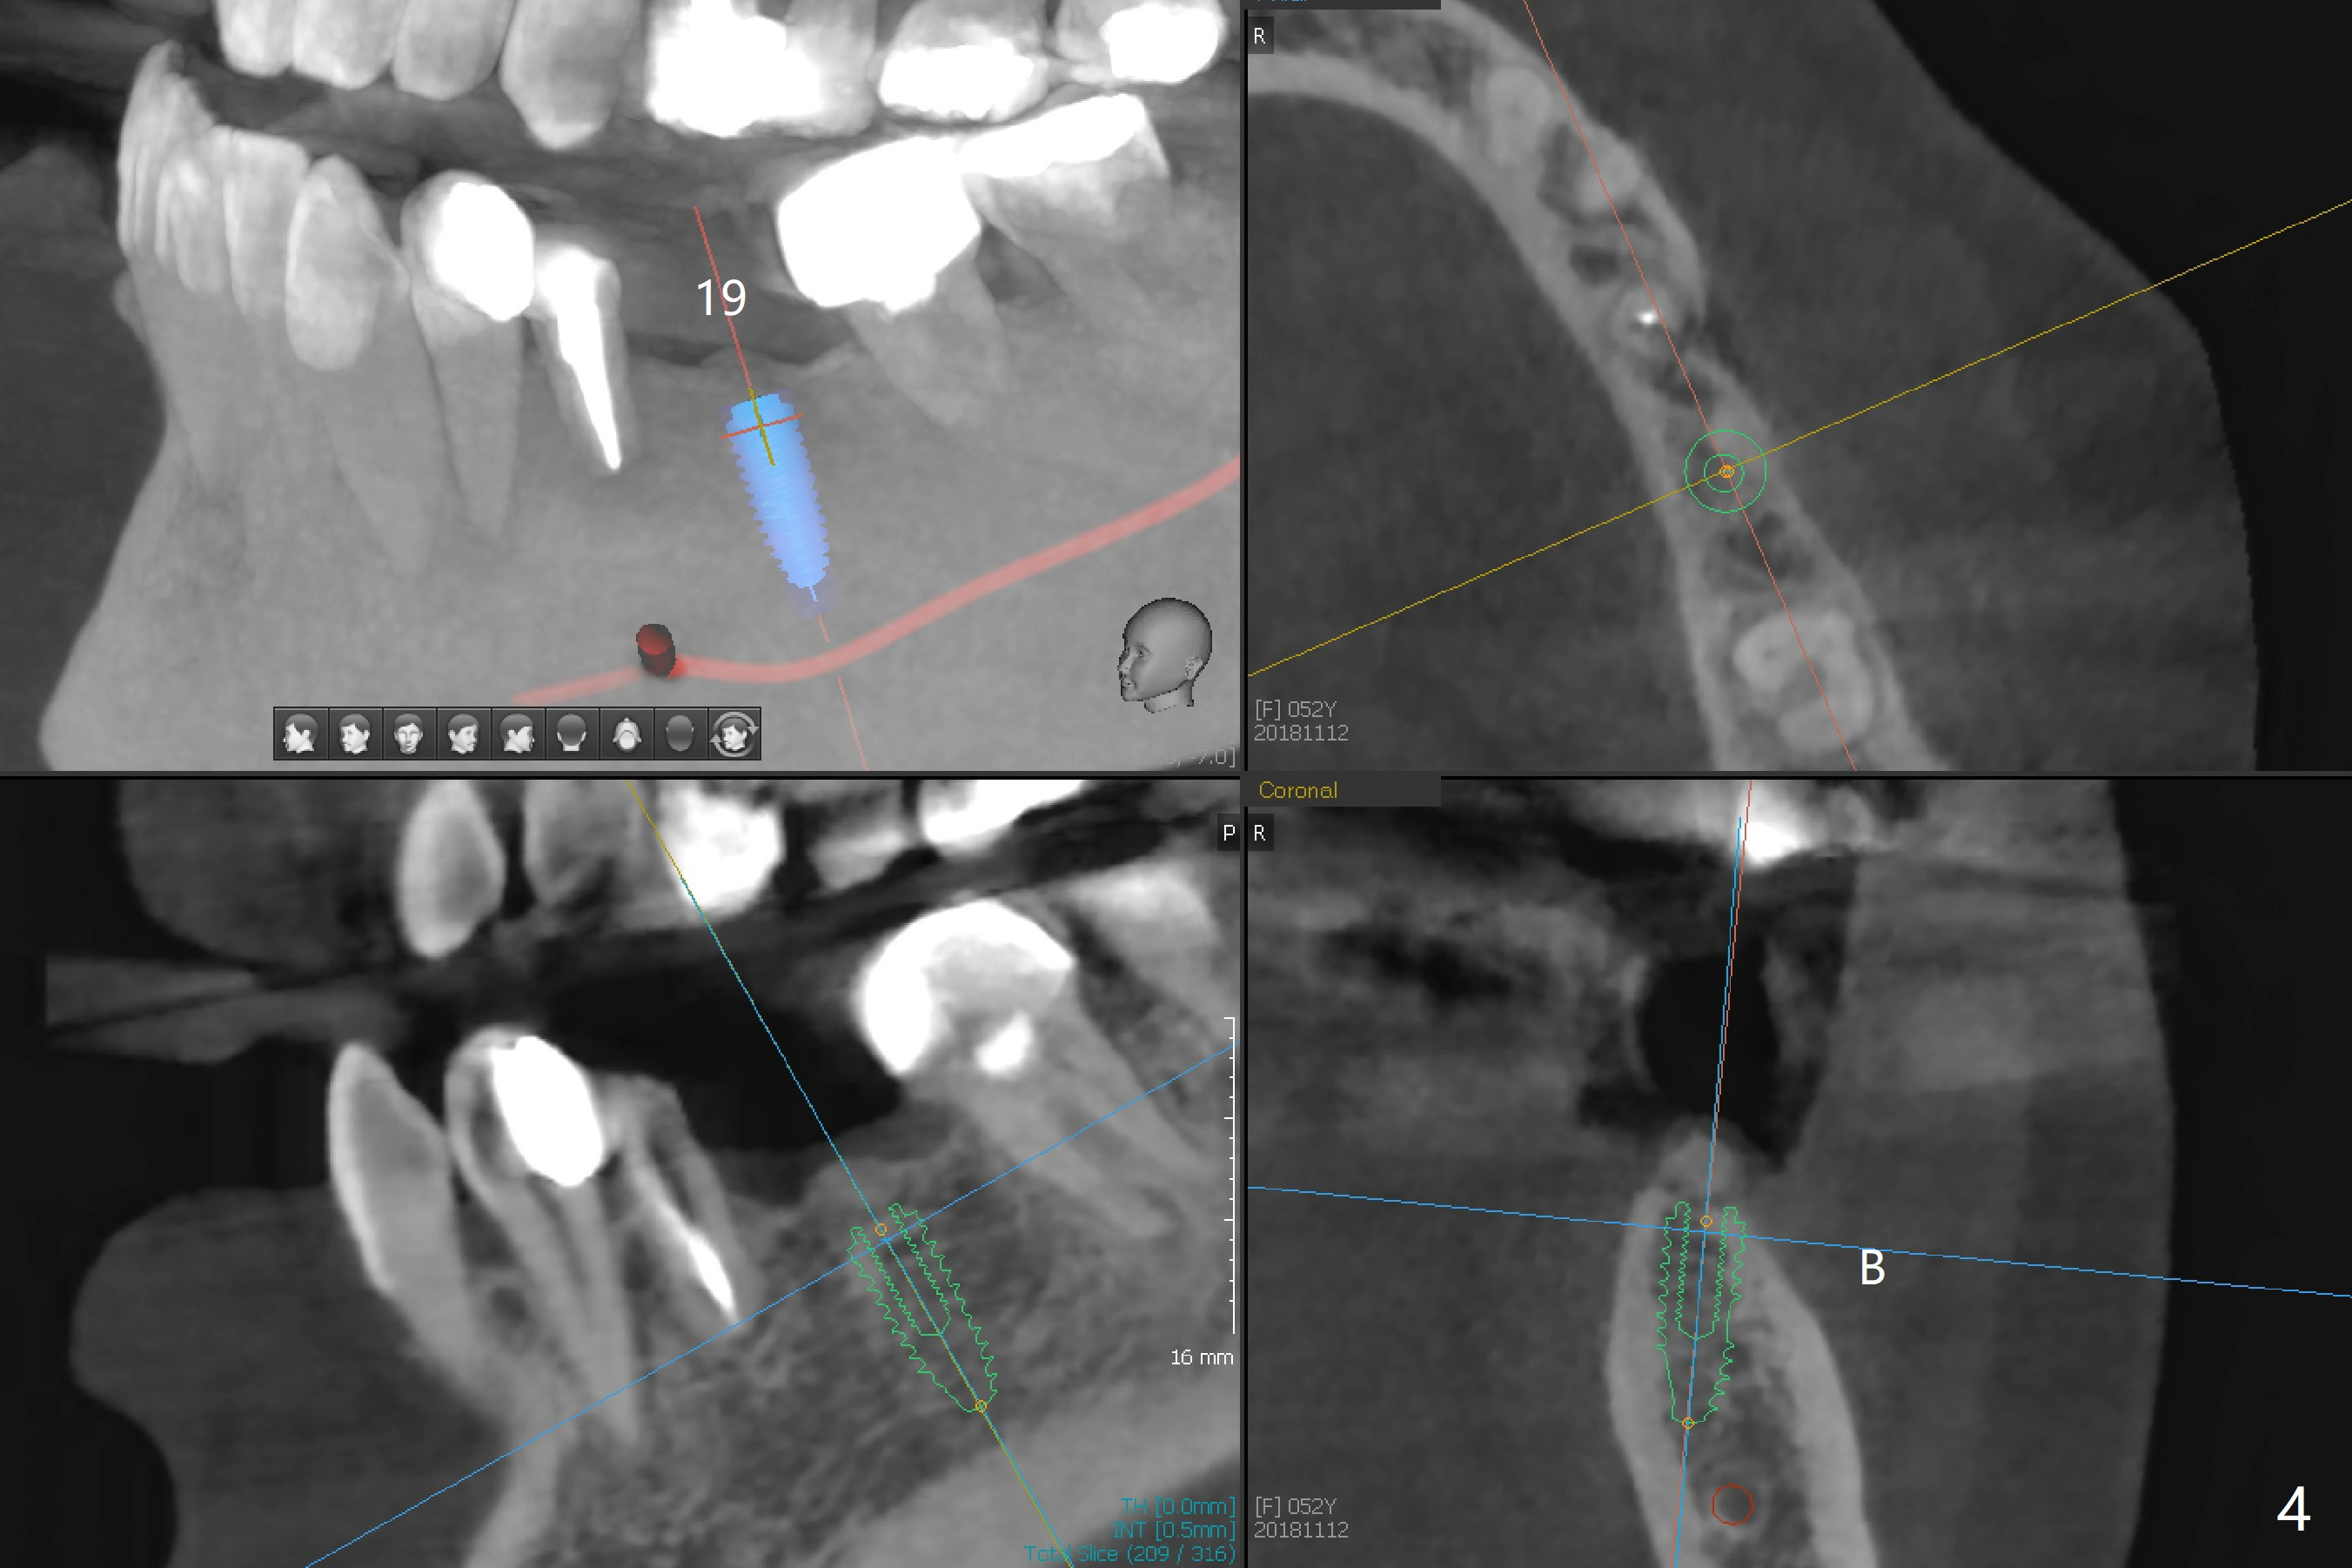

A 52-year-old woman requests an implant at #19 (Fig.1). Her other 2 concerns are the diastema between #5 implant crown and the tooth #6 (Fig.1 (^),2) and whether the tooth #20 is stable enough for crown after sectioning #18-20 FPD and RCT (Fig.1,3 (disto(*)-buccal (B) bone loss)). The ridge at #19 seems to be narrow; a 4x10 mm IS implant appears to be appropriate for the site (Fig.4). Since Magicore has a narrow core and aggressive fins, a 4.0 or 4.5x9(3) mm implant is apparently a good fit. After osteotomy, remove guide, use perio probe to determine crest level and place Magicore